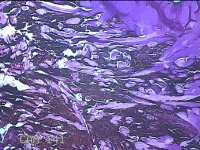

右手臂伸侧肿物

性别

女

年龄

27岁

临床诊断

纤维瘤病

一般病史

下腹部坠胀三天。

标本名称

大体所见

灰褐色肿物0.5x0.3x0.2cm一个,表面糜烂。

图2